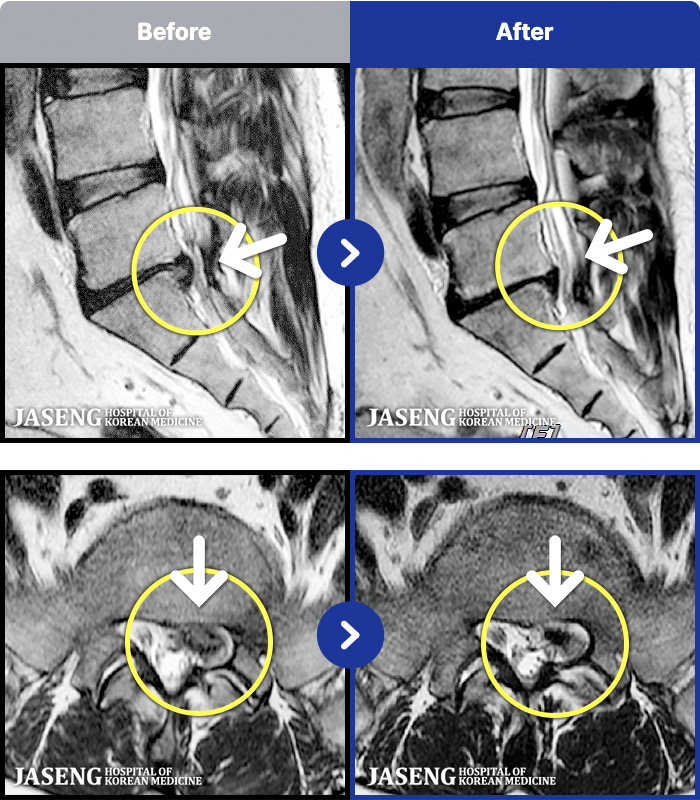

188 MRI ũ ʸ Ȯϼ.

ȯںп Ǹ ǿ ԿǾ, ο ġ ۿ Ƿ ġḦ Ͻñ ٶϴ.